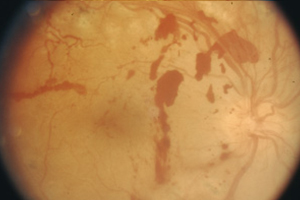

Nicht proliferative Retinopathie

Durch die zunehmende Schädigung der Gefäßwände können feine Ausbuchtungen der Gefäßwände entstehen (Mikroaneurysmen). Platzen kleine Äderchen, so kann man in der Netzhaut typische punktförmige Einblutungen erkennen. Eine verstärkte Durchlässigkeit der Blutgefäßwände führt zu einer Ablagerung von Flüssigkeit (Ödem) und Fettablagerungen im Netzhautgewebe. Diese Form der diabetischen Retinopathie wird als nicht proliferative Retinopathie bezeichnet. "Nicht proliferativ" bedeutet, dass noch keine neugebildeten Blutgefäße wachsen. Oft ergeben sich in diesem Stadium noch keine oder nur leichte Sehstörungen, die gut behandelt werden können.

Nicht Proliferative Retinopathie – Augenärztliche Gemeinschaftspraxis | Dr. Heuring, Dr. Jung & Kollegen

Ausgeprägte nicht proliferative Retinopathie mit ausgeprägten Fettablagerungen